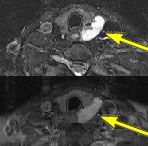

FINDINGS: The ultrasound (not shown) revealed a large solid mass behind the left lobe of the thyroid. Fig. 1-2 are MRI images of the neck demonstrating a mass behind the left thyroid lobe with hyperintensity on T2 weighted and STIR images (Fig. 1, 2 top) and enhancement higher than the thyroid (Fig. 2 bottom). Fig. 3-4 are Sestamibi images with Fig. 3 being coronal (top) and axial (bottom) SPECT images and Fig. 4 the early and delayed static images demonstrating persistent activity in the mass on delayed images while the thyroid activity washes out (arrows).